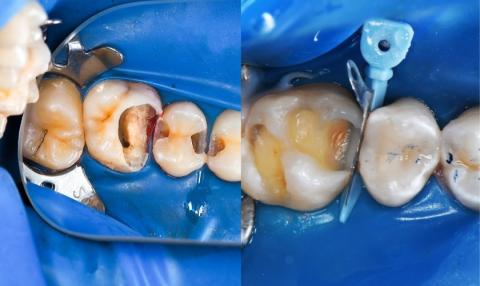

My name is Carlo, and this also happened to me. A dental friend advised me to remove my infected tooth. When I consulted other dentists, they also suggested extraction. The reason? They said my bone level was shallow and the infection inside the tooth was severe.

But I started to ask: Is removing the tooth always the best solution? Or is it simply the cheaper option?